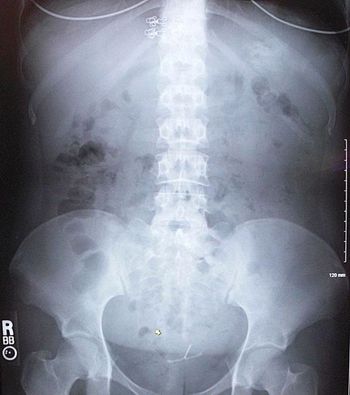

The patient has had 10 episodes of bleeding in the past 24 hours. Can you find clues to the underlying problem in the history and on the CT scan?